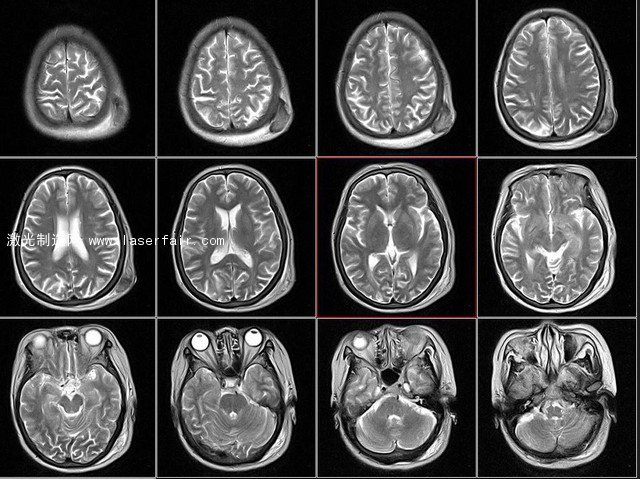

富蘭克林學院的科學家借助核磁共振技術掃描出一位40歲男子的2D腦部切片,再用計算機組合成為腦白質的3D模型。然而到這里出現了一個難題:人腦3D數據太過龐大和復雜,即使查看或者分享已經很困難,更不用提3D打印出來了。人們總是在說,3D打印技術擅長制造復雜的形狀,這次卻被復雜形狀所打敗。

人腦核磁共振切面圖 圖源ququliao.com